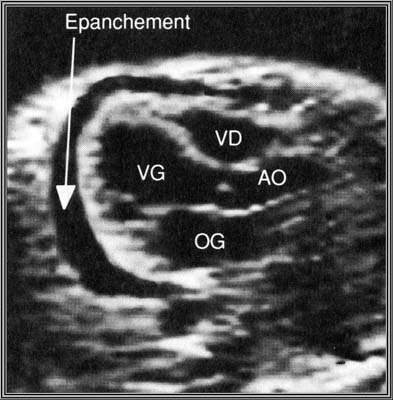

Epanchements péricardiques